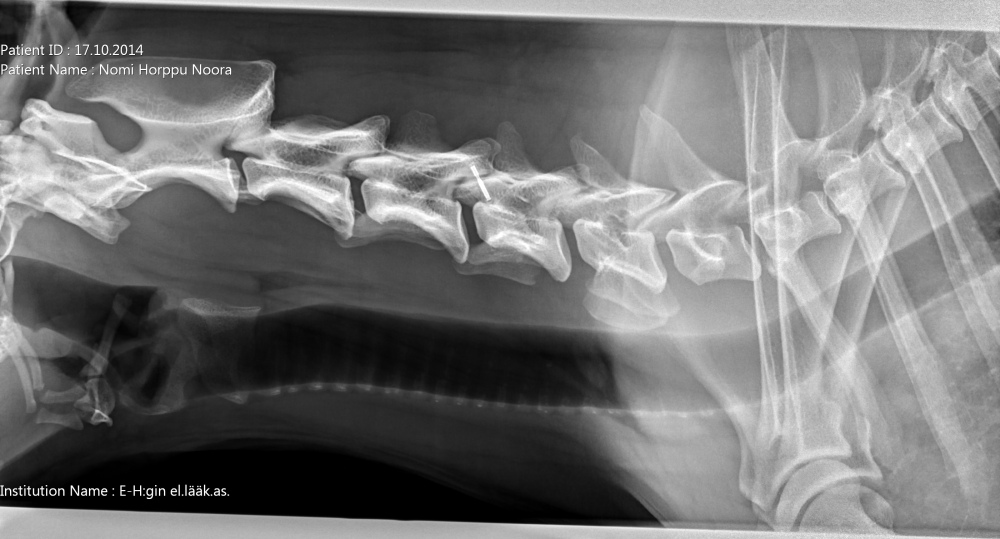

Niskasta otettu taivutuskuvat 17.10.14:

kaularanka1

kaularanka2

kaularanka3

Quti viety lääkäriin, koska vingahtelee kääntäessän päätään. Koko selkä kuvattiin, ei muutoksia. Oireiden jatkuessa kaularanka

magneettikuvattiin. Kuvanneen eläinlääkärin mielestä Nomilla on välilevyrappeuma ja kaikki harrastaminen mietittävä uudelleen.

Halusimme toisen mielipiteen Timo Talviolta, joka halusi ottaa Nomin kaularangasta taivutuskuvat. Talvion mukaan kyseessä ei ole

välilevyrappeuma vaan taivutuskuvissa näkyy kaularangan nikamien 5 ja 6 välillä liukuma. Lääkekuurin ja levon jälkeen voi

harrastamista jatkaa normaalisti. Talvion lausunto:"Kyse on nikamien välisestä "löysyydestä". Selkärangan rakenteelliset

viat ovat pääsäänöisesti perinnöllisiä, mutta tällainen lievä nikamien välinen liikkuvuus ei sellaisenaan ole perinnöllistä,

toki perintötekijät voivat altistaa tämänkaltaisen tilan kehittymiseen."